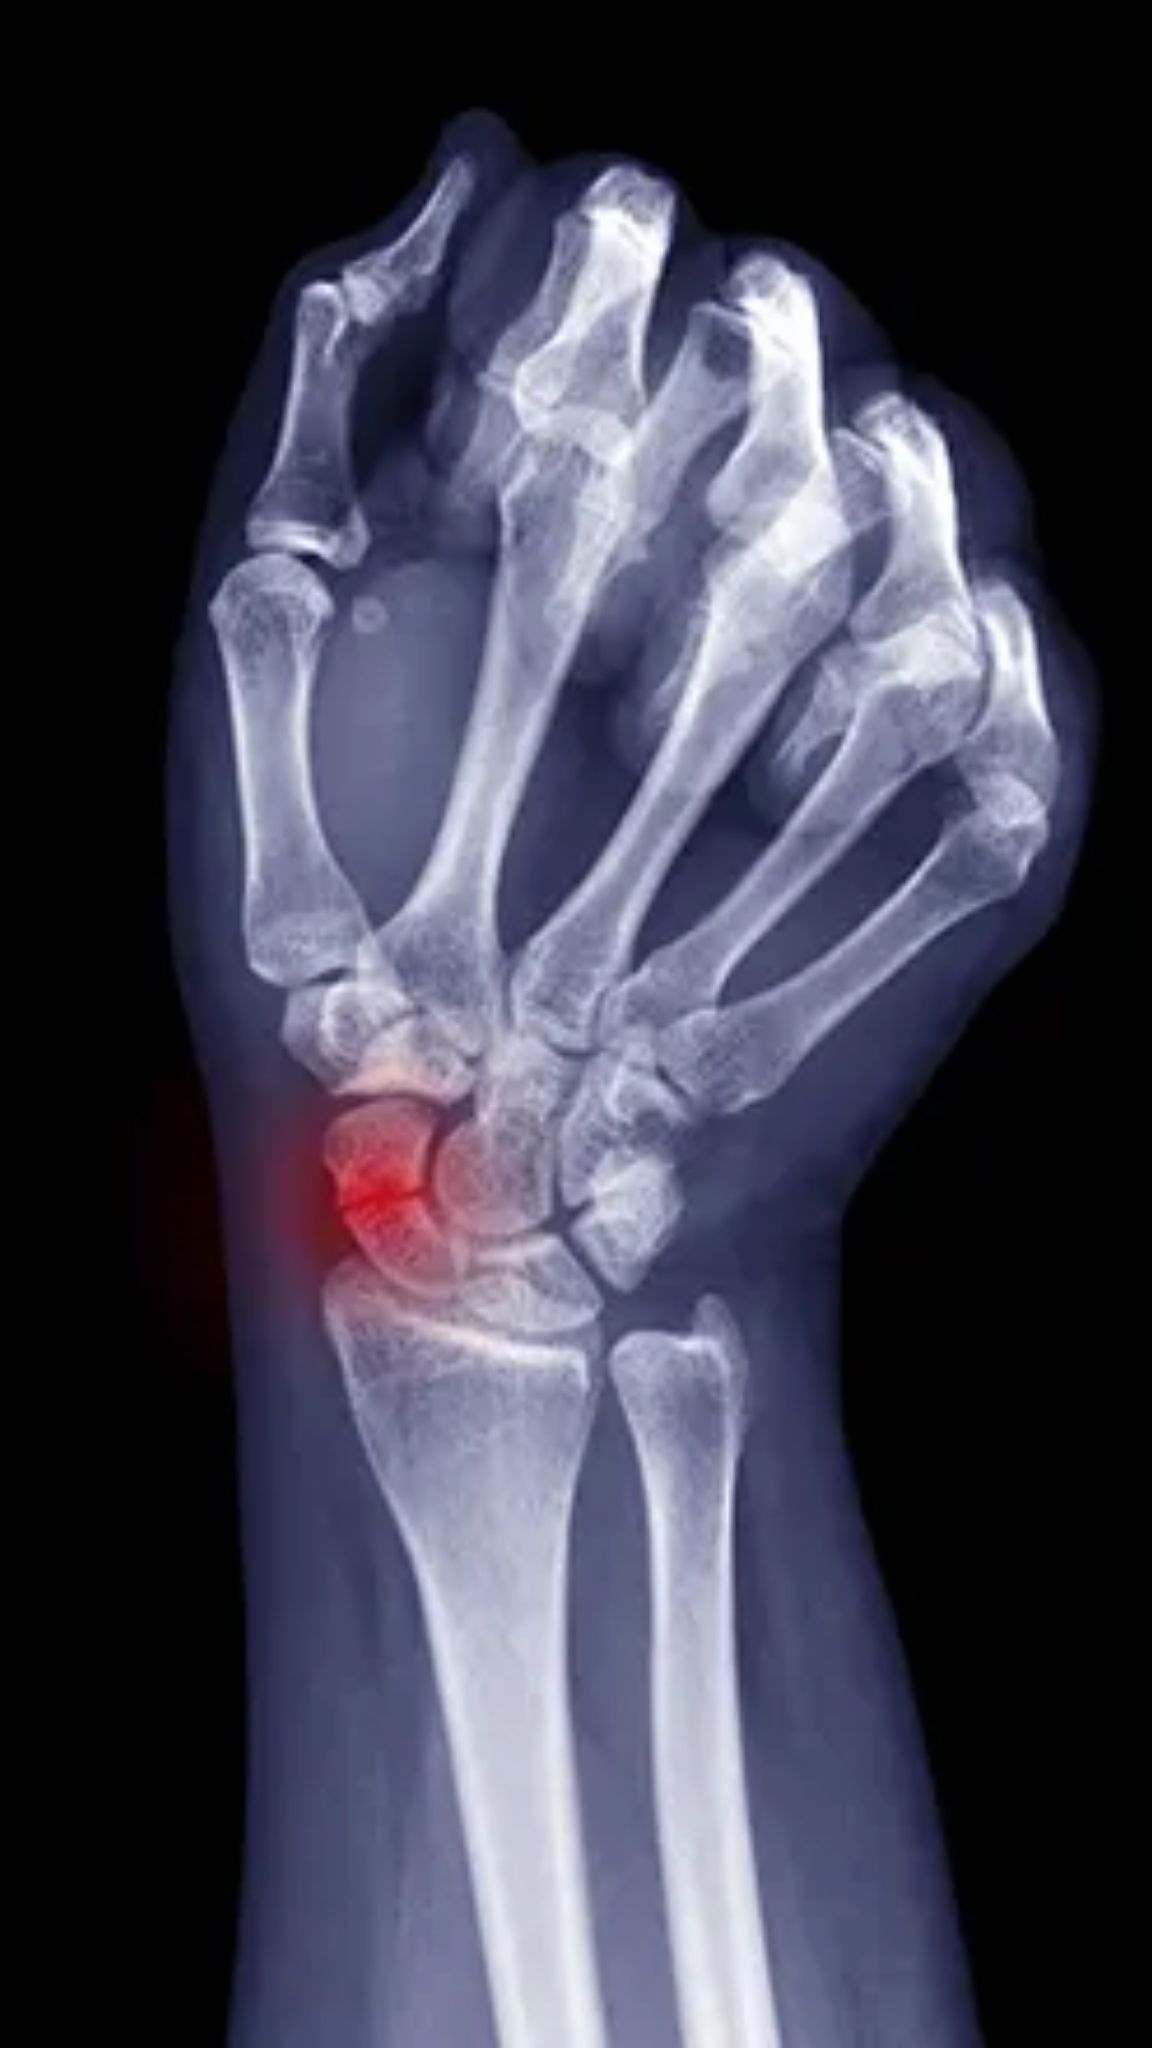

A fratura do escafóide é a fratura mais comum entre os ossos do carpo (o conjunto de oito pequenos ossos que formam o punho). O escafóide está localizado na base do polegar, em uma região conhecida como “tabaqueira anatômica”. A lesão ocorre frequentemente após uma queda com a mão espalmada, onde o impacto é transmitido diretamente para esse osso, causando sua quebra.

O diagnóstico correto é fundamental e começa com o exame clínico do ortopedista, que palpará a região específica. Exames de imagem são indispensáveis. O Raio-X deve ser feito em incidências especiais para visualizar o escafóide, pois fraturas sem desvio podem não aparecer nas radiografias iniciais. Em casos de suspeita clínica forte com Raio-X normal, a Tomografia Computadorizada (TC) ou a Ressonância Magnética (RM) são solicitadas para confirmar a lesão.